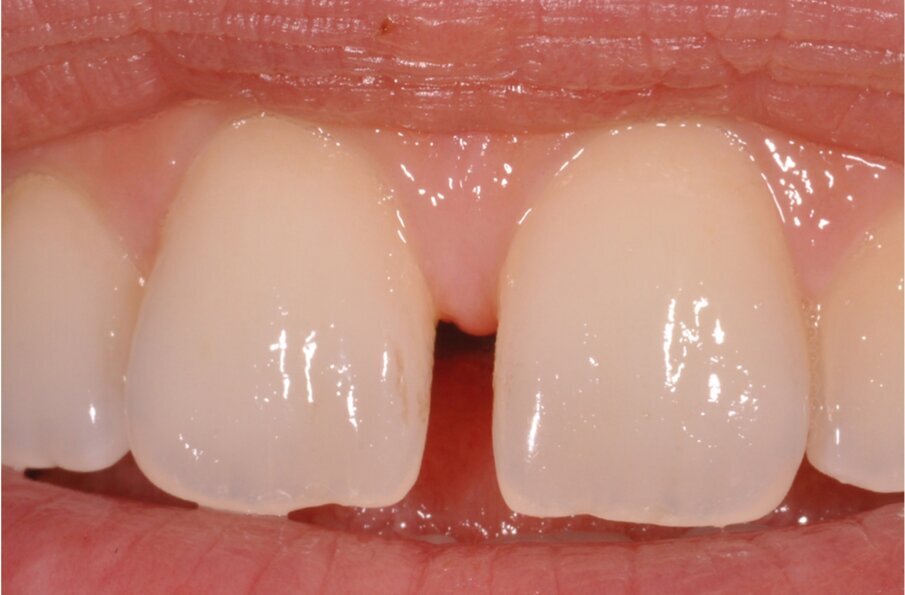

Case 2: Single shade restorations on a micro diastema where wax is not feasible (1 hour chair time)

Case 2, Fig. 1.

Case 2, Fig. 2.

Case 2, Fig. 3.